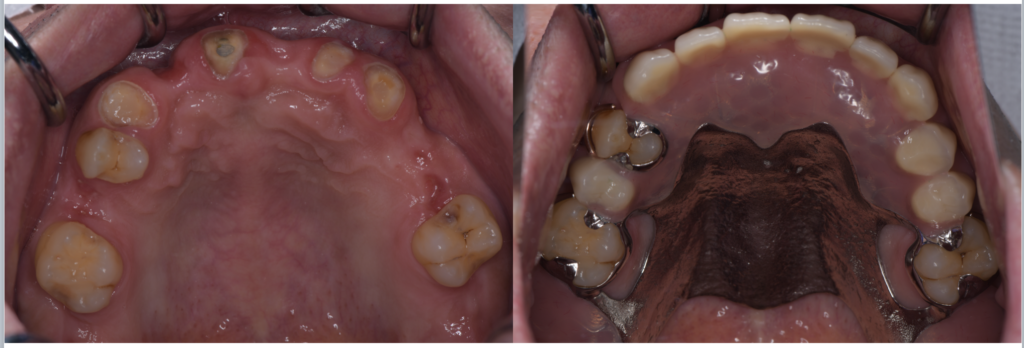

奥歯をセラミックで治すメリットとは?

1. 奥歯でもしっかり噛める高い強度

「セラミックは割れやすいのでは?」という不安を持つ方もいますが、現在の歯科用セラミックは技術の進歩により非常に高い強度を持っています。特に奥歯には、ジルコニアなど噛む力に強いセラ…